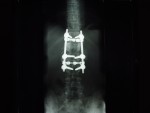

He has TWO rods in his back for support up and down... Two screws at the bottom of each rod and one at the top... He is in recovery at this time more than likely still...

The hardware is coming out! On April 28th I'm gettin' this monkey off (out of) my back. Hopefully it is the source of the leg pain that has slowed the recovery process.

DSC09489.JPG

The Monkey: Side View

DSC09486.JPG

The Monkey